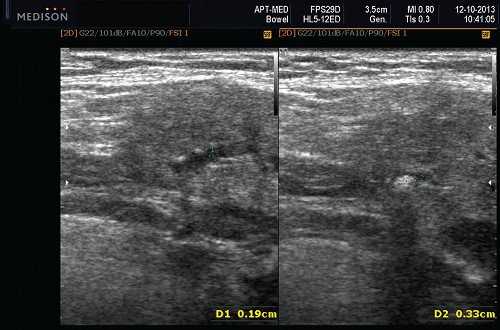

- обструктивные сиаладениты, развивающиеся при затруднении оттока слюны при обструкции выводного протока камнем (рис. 5-7) или сгустившимся секретом, а также вследствие рубцового стеноза протока. По распространенности процесса различают очаговый, диффузный сиаладениты и сиалодохит - воспаление выводного протока. Течение процесса может быть острым и хроническим;